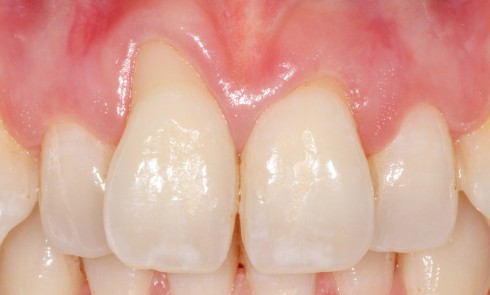

Article réservé à nos abonnés Relation ortho-parodontale. Réflexion autour d’un cas clinique

Parodontologie La parodontologie Hospitalo-Universitaire à l’École de médecine dentaire de Marseille est dirigée par le Pr Virginie Monnet-Corti. Elle s’appuie...